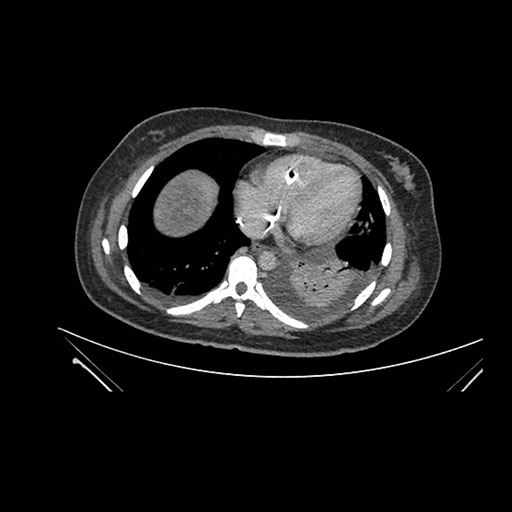

Axial Arterial